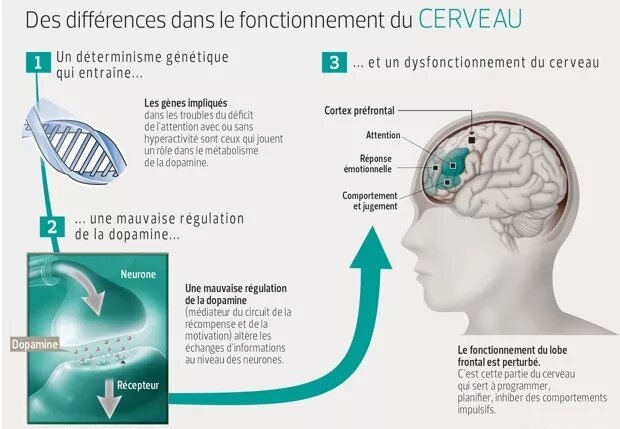

► C’est un déterminisme génétique (donc héréditaire), qui entraine, du point de vue neurologique, une mauvaise régulation de deux neurotransmetteurs principalement (excès ou carence) , la Dopamine et la Noradrénaline, notamment au niveau du lobe frontal et spécialement sa partie derrière le front, le cortex préfrontal (schéma ci-contre). – La Dopamine sert à réguler les circuits de la récompense, du plaisir, de l’énergie, de l’attention, de la vigilance et de la motivation. – Leur présence irrégulière dans les connexions entre les neurones au niveau de l’axone (schéma ci-dessus) entraine une inconsistance de l’attention, du plaisir et de la motivation, notamment pour les tâches ou les relations de la vie de tous les jours. ► Le cortex frontal sert à programmer, planifier, inhiber des comportements impulsifs, mais aussi avoir une bonne flexibilité mentale. Il doit en effet être capable de s’interrompre si quelque chose de prioritaire survient en pleine action. — Pour être attentif, on a besoin d’une bonne transmission de la dopamine dans ce cortex frontal, ce qui n’est pas souvent le cas avec le TDAH. – Cela se traduit de manière différente selon que l’on est dans une phase hyperactive ou hypoactive : – Si je suis hypoactif, c’est-à-dire avec peu d’énergie, je pense à une chose à faire qui me fait penser à autre chose, puis d’autres pensées arrivent encore. – Un haut potentiel associé à une des 8 formes formes d’intelligences recensées (mathématique, verbale, musicale, corporelle, visuelle, interpersonnelle, intrapersonnelle), peut construire une arborescence d’idées créative. – Mais souvent au final je n’ai rien fait, car je suis resté dans ma tête, et, de plus, je n’ai souvent rien mémorisé, car ce sont des pensées furtives non propices à la mémoire de travail. – Si je suis hyperactif, je commence une tâche, je l’interromps pour commencer autre chose puis autre chose sans lien avec la tâche prioritaire initialement commencée (hyperactifs). – j’ai fait une multitude de tâches ou j’ai parlé abondement, la plupart du temps sans intérêt par rapport à mes priorités et aux attentes des autres personne. ► Du point de vue neurologique, les fonctions exécutives sont regroupées en 6 familles (avec l’acronyme : A.F.F.A.M.É.E) : – ACTIVATION : s’organiser, structurer, synthétiser, prioriser, décider, initier la tâche en gérant le temps – FOCUS : maintien de l’effort et de la vitesse d’exécution, ou basculement vers une tâche prioritaire – ACTION : autorégulation des actions, ralentir, s’activer ou s’adapter selon les situations/personnes – MÉMOIRE : capacité à conserver et rappeler l’information en mémoire durant une tâche/conversation – ÉMOTIONS : savoir moduler l’émotion pour ne pas s’emporter facilement, savoir gérer la frustration – EFFORT : ne pas perdre l’intérêt dans la tâche et faire face aux difficultés dans un temps donné  ► Chacune de ces 6 familles de fonctions exécutives peut poser un problème si on a un TDAH. On parle aussi de syndrome dysexécutif. ⇒ Chacun peut faire son propre bilan neuropsychologique chez un neurologue moyennant finance, mais on peut résumer ci-dessous les principaux problèmes que rencontre la majorité des enfants et adultes TDAH : – Problèmes d’attention focalisée (concentration) et divisée (suivre plusieurs informations en simultané) – Problèmes de gestion des informations stockées dans la mémoire à court terme (mémoire de travail) – Capacité d’inhibition : il s’agit d’une difficulté à empêcher ou à freiner des comportements et paroles inadaptées. – Problèmes dans la formulation d’objectifs, l’anticipation, l’élaboration de stratégie et la prise de décision – Problèmes dans la planification, l’organisation, la gestion des priorités et la gestion du temps. ► Cette liste de déficits est insupportable pour ceux qui ont misé sur un style de vie ou un type de métier qui n’autorise pas ces dysfonctionnements. – Ces déficits des fonctions cognitives et exécutives peuvent être un obstacle si on veut construire une vie trop conventionnelle nécessitant de la rigueur et de la régularité, avec beaucoup de frustration et le sentiment de ne pas s’accomplir. – D’où la nécessité de bien se connaitre pour faire des choix de style de vie, d’objectifs et de métiers compatibles avec cette particularité neurologique, ainsi que respecter ses besoins et valeurs. – Toute forme de forte et saine motivation peut permettre de générer la dopamine et noradrénaline nécessaires pour avancer durablement sur ses projets. – Une bonne hygiène de vie, de l’exercice physique, des pratiques psychocorporelles pour calmer le mental permettront d’atténuer cette inconsistance en neurotransmetteur (voir plus loin le manuel d’auto-coaching). |